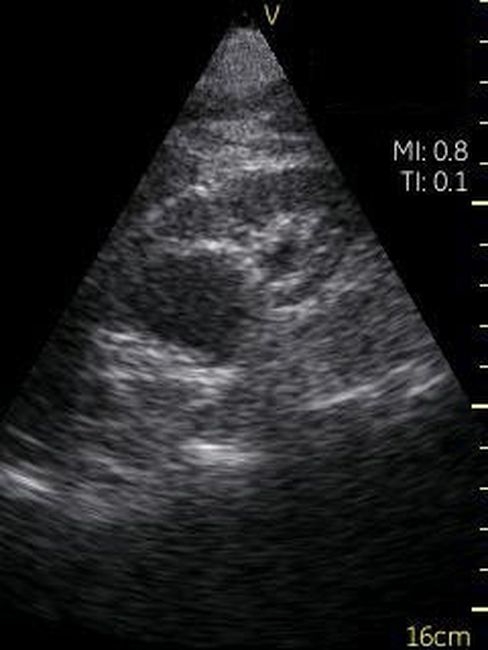

Визуализация Vscan:

· Черно-белый режим для визуализации анатомических структур в реальном времени.

· Поле зрения в черно-белом режиме: до 75 градусов с максимальной глубиной 25 см.

Области клинического применения УЗИ Vscan:

· Органы брюшной полости.Мочевой пузырь.